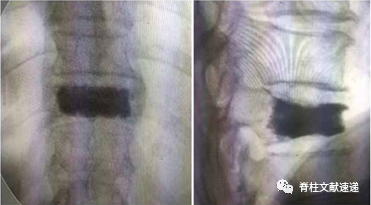

图注:图A为PKP术后CT结果显示PKP孔道未累及椎间小关节;图B显示PKP孔道累及左侧椎间小关节;